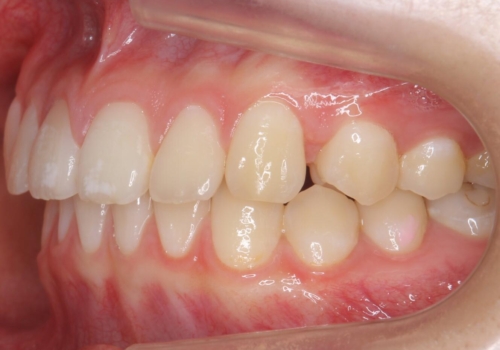

- 10代女性

- ワイヤー矯正

- 前歯のすき間を気にして来院。

全体矯正ではなく部分矯正で治療することになりました。

その代わり、すき間をすべて閉じるのは難しく、両脇の目立たないところに集めて治療終了しています。